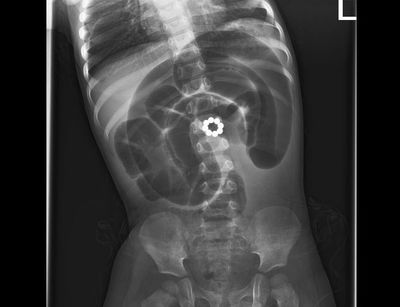

בן שנתיים בלע מגנטים והובהל לבית החולים, שם הבהירו כי חיין בסכנה, מכיוון שכאשר הפעוט בולע יותר ממגנט אחד, הם נצמדים זה לזה בתוך מערכת העיכול ועלולים לגרום לקרעים במעיים ואז תכולת המזון במעיים נפלטת אל הבטן, לאחר הניתוח, חיי הפעוט ניצלו (חדשות)